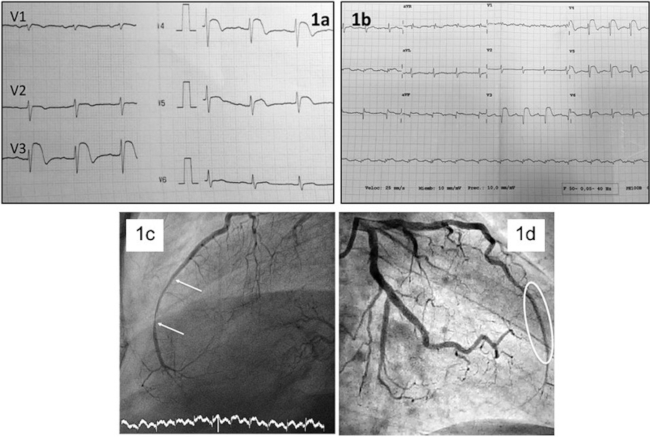

Se trata de un varón de 71 años que acudió al servicio de urgencias con dolor precordial persistente y sensación de falta de aire. Su electrocardiograma mostró supradesnivelación del segmento ST en las derivaciones de V2 a V4 (Figura 1a). Tenía como antecedentes hipertensión arterial y tabaquismo. Con diagnóstico de SCACEST fue trasladado a nuestro centro para angioplastia primaria. En la coronariografía se evidenció una estenosis severa en el segmento distal de la arteria descendente anterior (LAD) que se trató con un stent farmacoactivo (Figuras 1c y 1d). La evolución posterior fue atípica, persistiendo la supradesnivelación del segmento ST pero sin aparición de ondas Q de necrosis (Figura 1b) y sin elevación de troponina. A los 7 días reaparecieron los síntomas (dolor precordial refractario, disnea y ortopnea). La TC detectó un cáncer primario de pulmón en el lóbulo superior derecho, infiltración miocárdica del tabique interventricular (Figura 2) y metástasis óseas y en glándulas suprarrenales. Durante esa hospitalización el patrón ECG fue similar al descrito en el ingreso previo (supradesnivelación segmento ST), probablemente debido a la invasión tumoral del miocardio. Aunque no se realizó biopsia de la masa pulmonar, los hallazgos de la TC indicaron que se trataba de un adenocarcinoma de pulmón. El paciente recibió tratamiento paliativo, falleciendo un mes después de la revascularización coronaria.